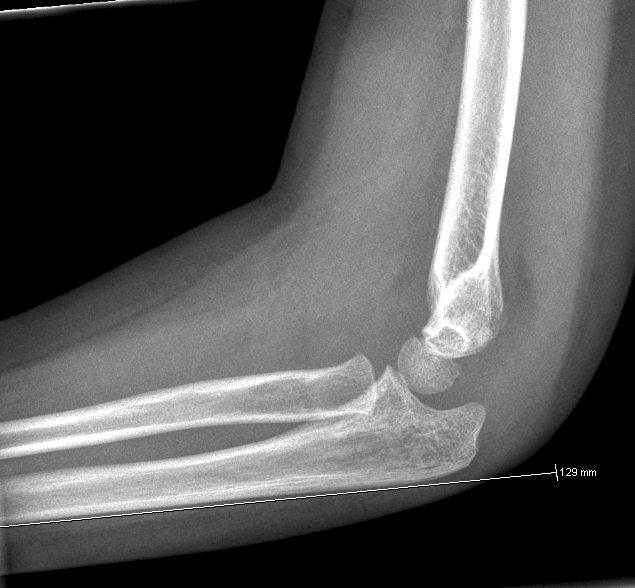

En linie gennem centrum af radius skal altid gå lige igennem capitulum humeri.

En linie langs forsiden af humerus går normalt igennem midterste 1/3 del af capitulum humeri, hvis capitulum ligger bagved skal der reponeres og osteosynteres i GA. Hos børn under 4 år tillades lidt større dislokation.

BOWING ULNA:

Normal:

Bemærk dislocation af radius. Skal reponeres i GA.